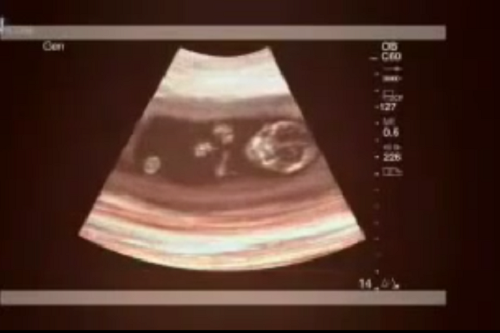

Một người mẹ trẻ mang thai ngoài ý muốn ở tuổi 13 nên quyết định đi phá thai. Tuy nhiên, sau ngày phá thai, cô phát hiện bụng mình to lên bất thường.